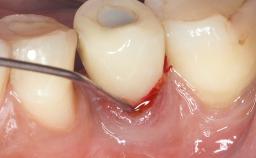

Reconstructive Surgical Treatment of Peri-Implantitis with Long-Term Follow-up

A 72-year-old female patient was referred to the specialist clinic with signs of peri-implantitis associated with implant 14. Two implants (sites 14 and 15) had been in function for three years. The patient was in good general health and was not taking any medication. She was a former smoker (12–15 cigarettes a day for 50 years) but had ceased smoking two years prior to implant placement. Her periodontal condition was stable, with no probing depths above 5 mm and a full-mouth plaque score (FMPS) of 35%.